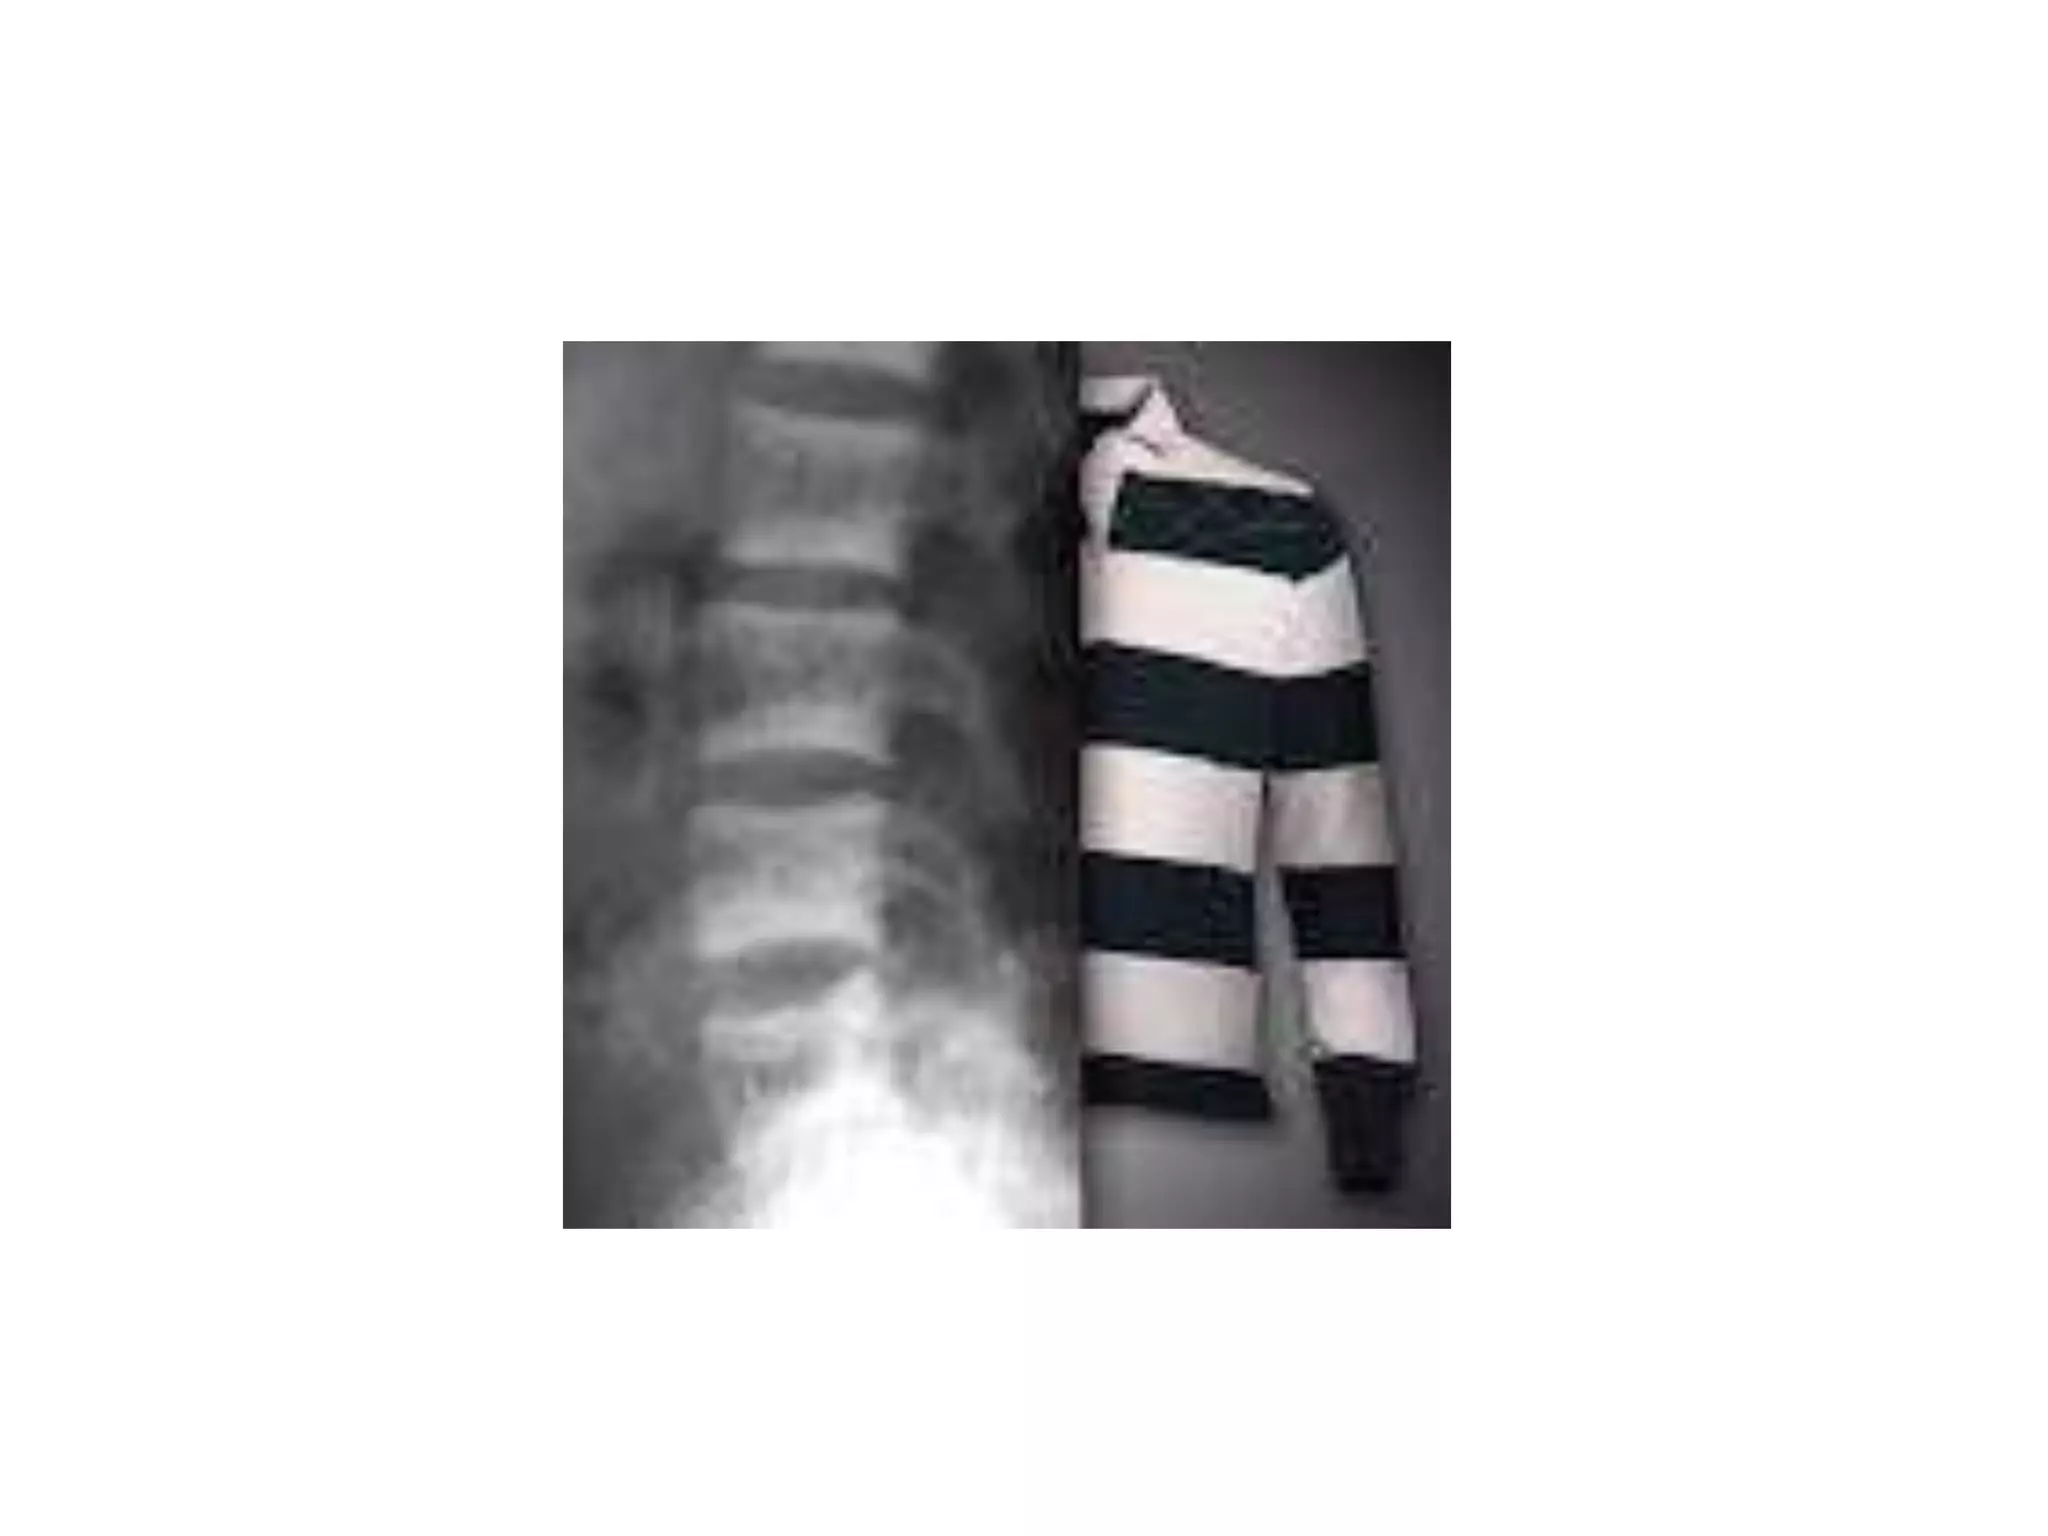

Acromegaly the vertebral bodies show mild

posterior scalloping